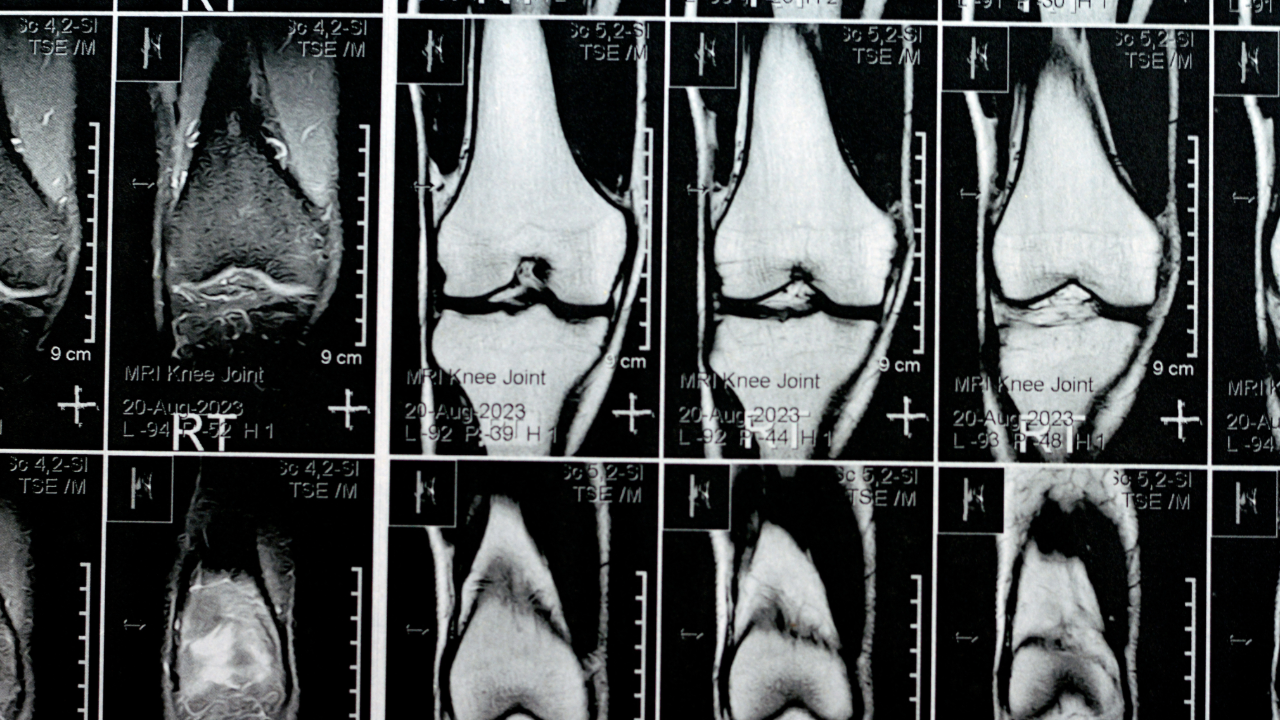

What an MRI Actually Shows

Knee MRI

An MRI (Magnetic Resonance Imaging) scan produces detailed images of the body's soft tissues, including:

• muscles

• ligaments

• tendons

• cartilage

• intervertebral discs

MRI scans are useful when doctors need to investigate structural problems such as:

• ligament tears

• disc herniations

• severe joint damage

• certain nerve compressions

However, MRI findings do not always explain a person’s symptoms. Studies have shown that many people without pain may still show abnormalities on MRI scans, particularly in areas such as the spine.

Because of this, MRI results must always be interpreted alongside a clinical assessment and physical examination.